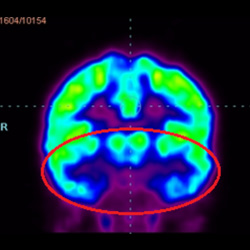

細(xì)胞治療后,藍(lán)色和黑色區(qū)域減少,并且看到更活躍的區(qū)域。這表明損傷減少并改善了大腦功能。

這證明細(xì)胞療法是治療腦癱兒童安全有效的方法。細(xì)胞療法可以更新大腦損傷的核心,并且可以通過 PET CT 掃描來監(jiān)測大腦的改善情況。這些細(xì)胞療法與標(biāo)準(zhǔn)治療一起促進(jìn)腦癱兒童的生長和改善。